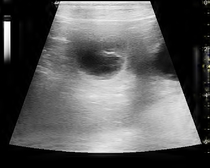

Ultraschalltermin Giya ist trächtig |

Ultraschall 9.2.22 Giya ist trächtig